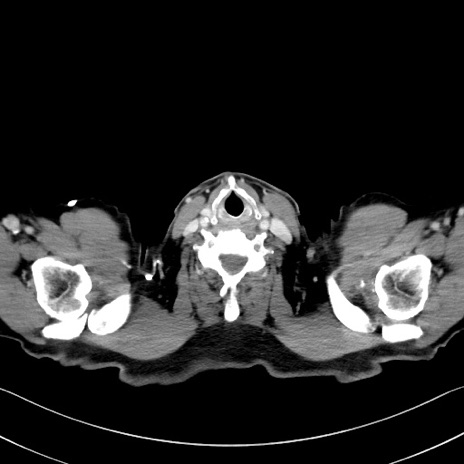

症例35(横断像)

【症例】70歳代 男性

【主訴】腹部膨満、嘔吐

【現病歴】昨日より腹部膨満感出現。本日増悪し、仙痛出現。嘔吐あり、受診。

【既往歴】糖尿病、胆摘後

【身体所見】BP 149/80mmHg、HR 74/min、BT 35.9℃、腹部:膨満、軟、圧痛なし。腸雑音減弱あり。上腹部正中切開瘢痕あり。

【データ】WBC 13500、CRP 1.72